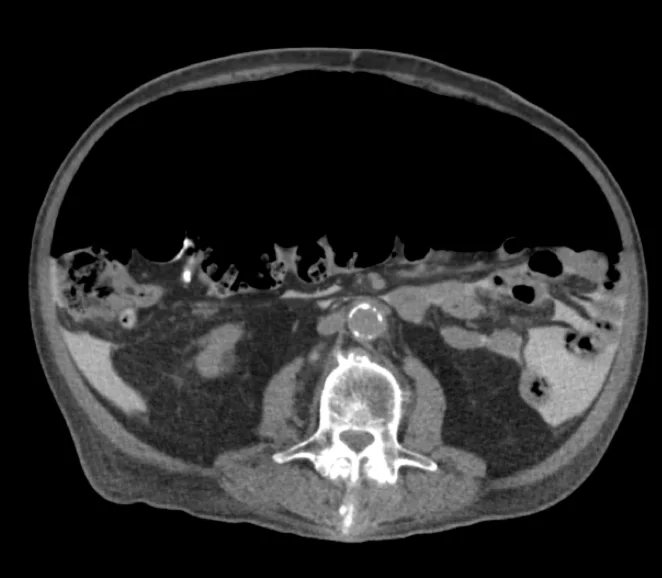

You are working one evening when an elderly gentleman is sent in by his nephrologist for abdominal pain.  The patient has a history of renal failure and is on peritoneal dialysis.  Last evening, he developed sudden, severe abdominal pain and was unable to perform PD at home.  Today, he went to the outpatient dialysis unit where they withdrew some fluid.  His nephrologist ordered a CT of the abdomen and pelvis which demonstrated the following:

Final diagnosis: Iatrogenic pneumoperitoneum from injection of air through peritoneal dialysis catheter

Case Conclusion:   The patient was noted to have a large amount of free air on his CT scan (which was actually a CT peritoneogram in which contrast was injected into the peritoneum via the PD catheter, thereby accounting for contrast in the peritoneal space).   The air was evacuated from his peritoneum via the dialysis catheter and his pain improved. An upper GI series performed with water-soluble contrast was negative for perforation.  The patient was admitted for serial abdominal exams and discharged to home the next day.  It was determined that the patient likely had inadvertently allowed air to enter his peritoneum via the PD catheter and he was re-instructed on proper technique.